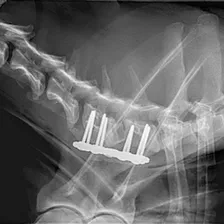

Cutting-edge surgical techniques supported by the latest evidence; TPLO for cruciate ligament tears. Management of patellar luxation, elbow, shoulder, hip & tarsal joint disease, MIPO techniques for complex fractures & limb deformities.